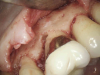

(7.) In cases in which an infrabony defect is inaccessible or surgical access would result in excessive removal of sound tooth structure, internal repair is the treatment of choice.

Figure 7

(8.) The defect is accessed through the pulp space and debrided with rotary or ultrasonic instruments.

(9.) The defect should be irrigated with saline as opposed to sodium hypochlorite because the portal allows for direct communication with the periodontal ligament space and a hypochlorite accident could occur.

(10.) A 90% TCA solution is applied using a paper point.

Figure 10